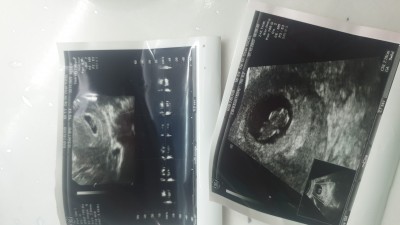

Merhaba anneler 11 haftada bebegime kiz dedi 12 haftada erkek dedi 14 haftada tekrar kiz dedi oncelik saqlik tup bebek annesyim doktor hem yumurtami catlatto cinsel iliski önerdi 5 gun sonra transfer yaptı bir kiz bir erkek bir kiz diyince acaba ikiz bebekmi die düşündük kese şeklide her gttimde bi fasulye seklinde bi yuvarlak merak ettim en çok kese bi yuvarlak olup bi fasulye seklinde olabilirmi her gttimde farkli kese ve ben doktora hic ikiz mi die sormadm

image

Bunlarda en.son gttim iki kese sekli